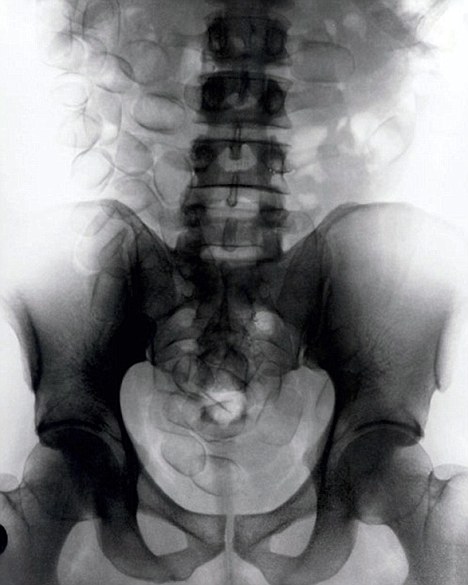

現(xiàn)年30歲的菲達利斯(Fidelis Ozouli)冒著生命危險將重達1公斤的毒品吞下,被抓后卻辯稱不知道吞下的是毒品。當時,曼徹斯特機場的海關(guān)人員看到毒販菲達利斯臃腫的肚腩,顯得很不自然,于是開始懷疑。檢查人員用X射線機照他的胃部時,發(fā)現(xiàn)了大量可卡因。目前他已被送往附近醫(yī)院,以確保排出所有的毒品。